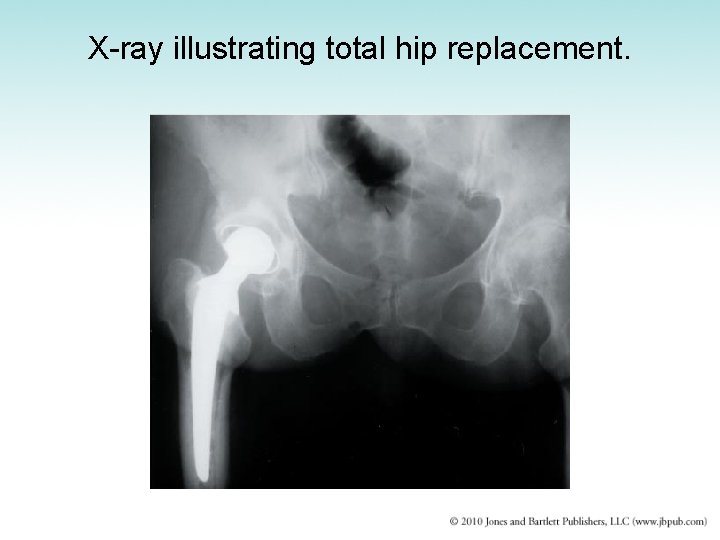

X-ray illustrating total hip replacement.